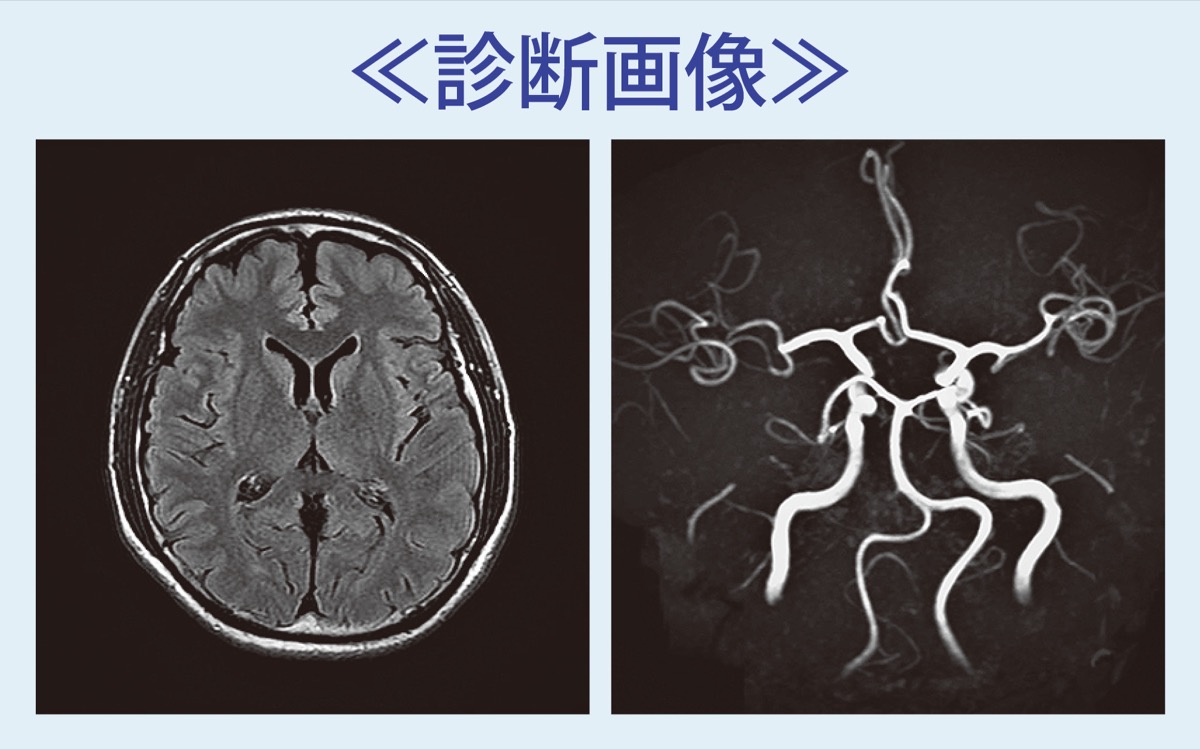

国内で年間約30万人もの人が脳の病気を新たに発症し、約10万人が命を落としているというデータがある。これを予防する手段のひとつが「脳ドック」の受診。発見できる病気にクモ膜下出血の原因となる脳動脈瘤、脳梗塞の原因となる脳血管狭窄症や虚血性変化、認知症と関連のある脳萎縮や脳腫瘍などがある。

クモ膜下出血は脳動脈瘤が破裂し、突然の激しい頭痛や意識消失で発症して3割の人が死亡する。後遺症が残ることもまれでない。高齢者だけではなく、若い人でも発症リスクがあるが、動脈瘤を見つけて適切な治療を受けることで破裂を予防できる。アルツハイマー型認知症の進行状況も把握することが可能だという。

放射線などを使わずに20分程度で検査できる「MRI脳ドック」は、これらの病気の早期発見・治療につなげるための”転ばぬ先の杖”。特に高血圧や高脂血症などの生活習慣病を抱える人や血縁者にクモ膜下出血を発症経験のある人、認知症が気になる人の受診を呼び掛けている。